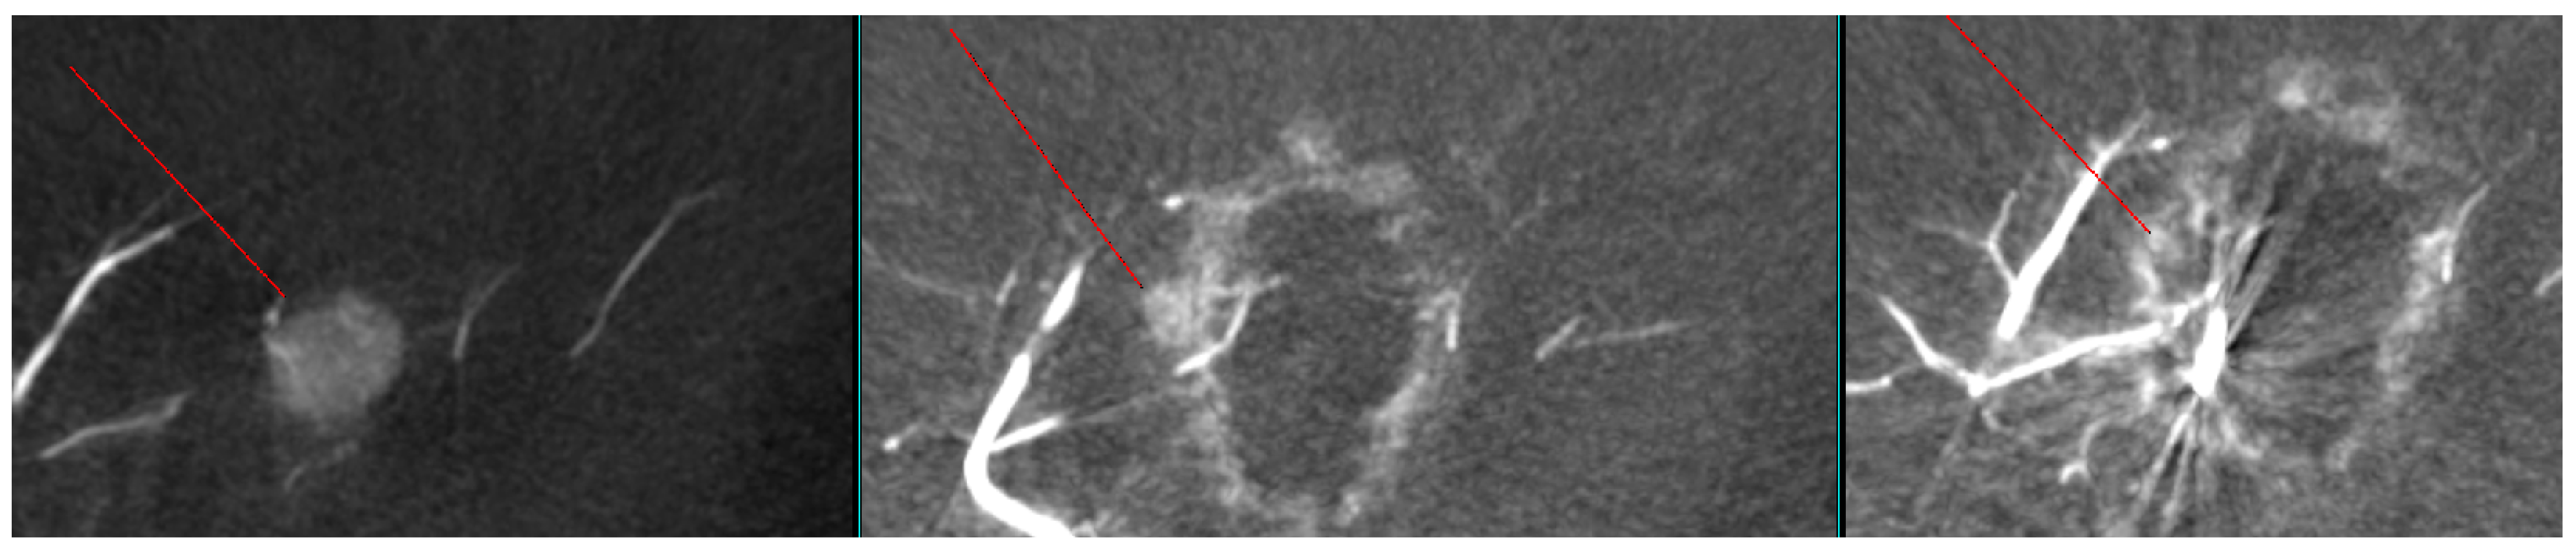

As shown in Figure 1, angio-CBCT allows for higher visibility of the target mass, as reflected in the ΔHU values. This can be visually confirmed in several cases. Representative cases in Figure 2 and Figure 3 demonstrate how the target mass is much more conspicuous to the operator on angio-CBCT compared to pre-procedural CT. In Figure 4, a mass, which was nearly invisible on pre-procedural CT, was identified through angio-CBCT, aiding the targeting process. Figure 5 shows a case where a mass with discordance between USG and CEUS was confirmed using angio-CBCT, leading to needle repositioning and achieving complete ablation. Finally, Figure 6 illustrates a case where a residual tumor was identified on angio-CBCT and re-ablation resulted in complete ablation.

Figure 3. CT images from other patient with hepatocellular carcinoma undergoing angio CBCT-guided RFA. (Top): pre-procedural CT (arterial phase). Red arrow and line = HCC mass (lesion 74.29 HU). (Bottom): intraprocedural angio CBCT. Red arrow = HCC mass (lesion 368.49 HU). ΔHU = 173.9 HU. (intra lesion − intra background) − (pre lesion − pre background).

Diagnostics 15 02898 g003